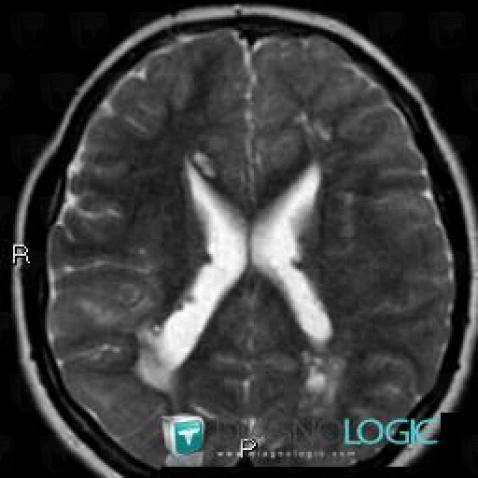

Here is the specific information in the key image above:

- Diagnosis Hamartoma, Location(s) Basal ganglia and capsule, with gamuts Basal ganglia T2W or FLAIR hypointense lesion

- Diagnosis Tuberous sclerosis, Location(s) Basal ganglia and capsule, with gamuts

Here is the specific information in the key image above:

- Diagnosis Tuberous sclerosis, Location(s) Corpus callosum, with gamuts Corpus callosum lesion

Here is the specific information in the key image above:

- Diagnosis Tuberous sclerosis, Location(s) Corpus callosum, with gamuts Corpus callosum lesion

Here is the specific information in the key image above:

- Diagnosis Hamartoma, Location(s) Basal ganglia and capsule, with gamuts Basal ganglia T2W or FLAIR hypointense lesion

- Diagnosis Tuberous sclerosis, Location(s) Basal ganglia and capsule, with gamuts